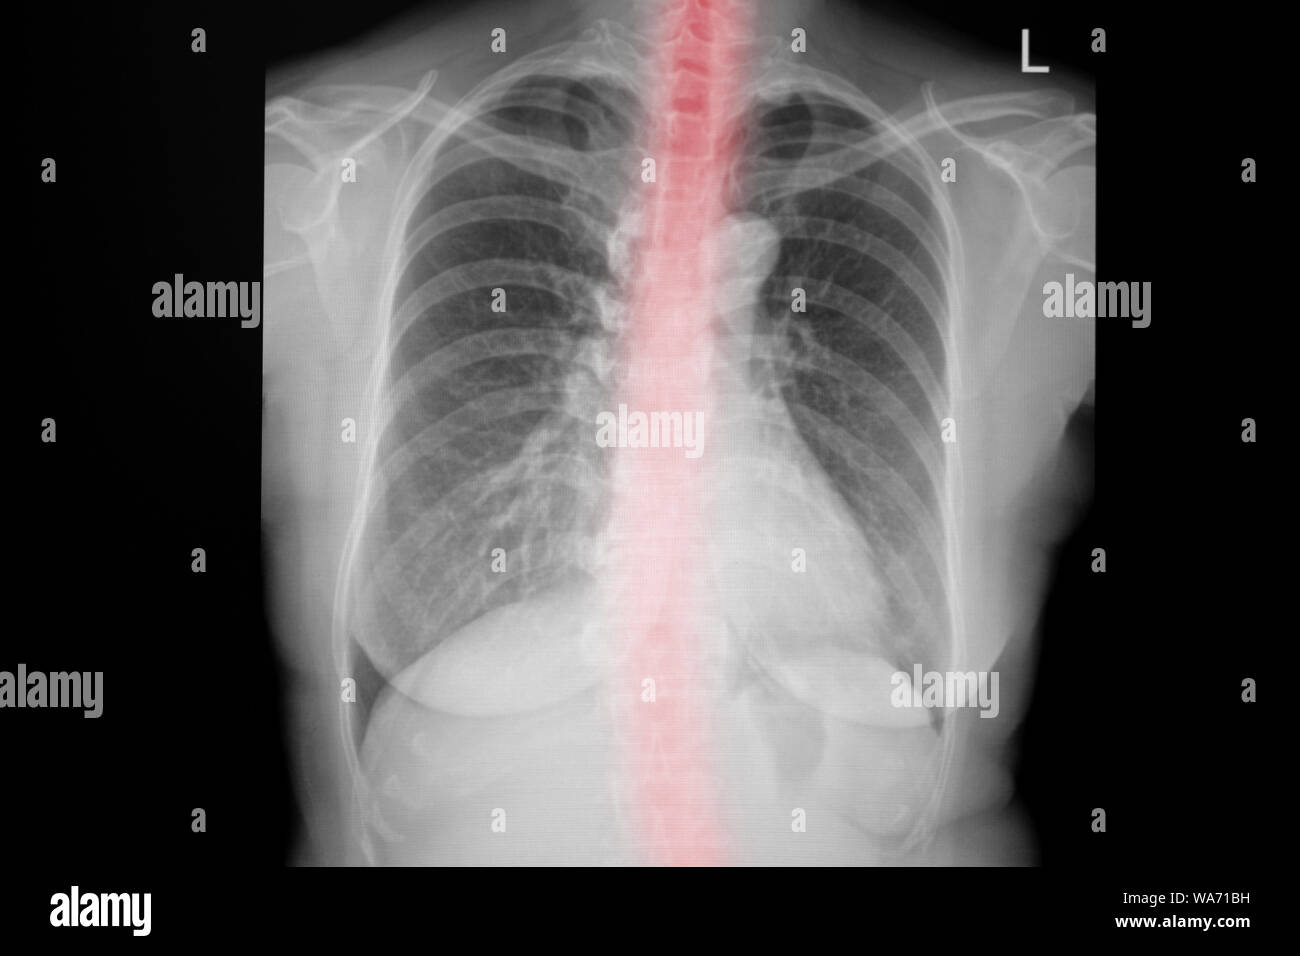

RMPF833F–Mise en scène mi-épanchement pulmonaire bilatéral en raison de syndrome pulmonaire à hantavirus (SPH), révélée dans l'AP La radiographie du thorax, 1994. Image courtoisie Centres for Disease Control (CDC) / D. Loren Ketai, M.D. ()

RMPF8351–Premières étapes de l'épanchement pulmonaire bilatéral en raison de syndrome pulmonaire à hantavirus (SPH), révélée dans l'AP La radiographie du thorax, 1994. Image courtoisie Centres for Disease Control (CDC) / D. Loren Ketai, M.D. ()

RMD0NWAJ–Cette radiographie pulmonaire révèle la mi-monté en raison d'épanchement pulmonaire bilatéral syndrome pulmonaire à hantavirus ou radiologique de la SPLI.

RMPF834T–Mise en scène mi-épanchement pulmonaire bilatéral en raison de syndrome pulmonaire à hantavirus (SPH), révélée dans l'AP La radiographie du thorax, 1994. Image courtoisie Centres for Disease Control (CDC) / D. Loren Ketai, M.D. ()